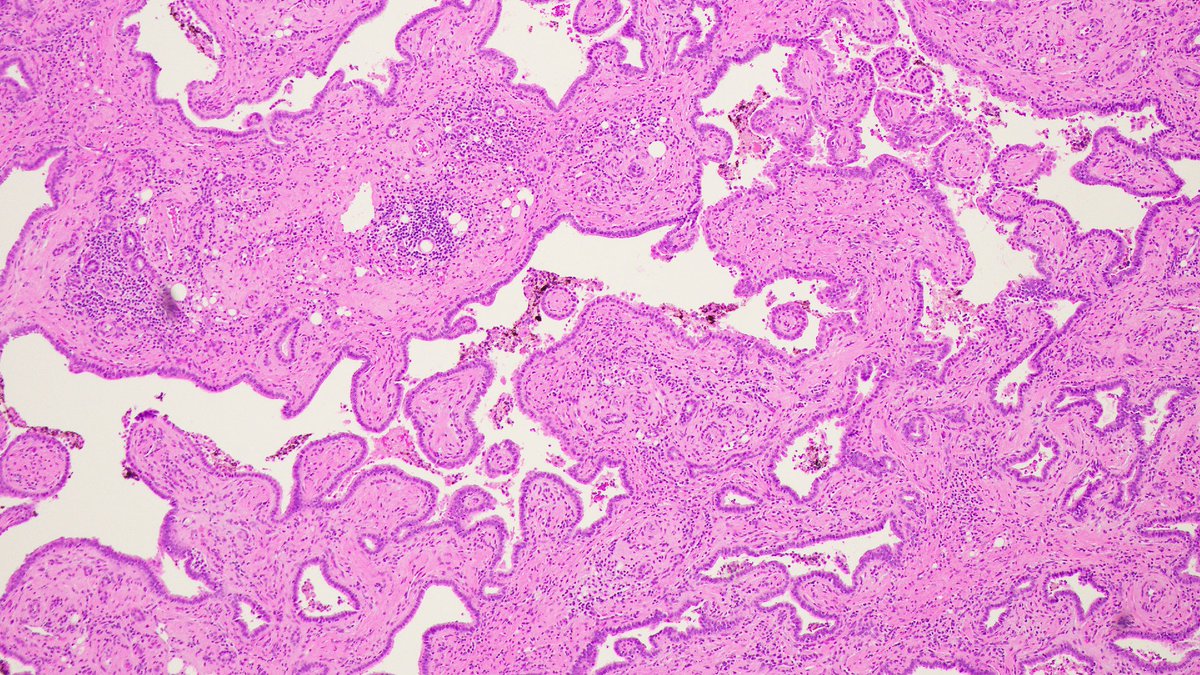

🔬EMORY CASE OF THE WEEK #53: 23F w/ no significant medical history with 12 cm mass in left lobe of liver. Answer the question below! Contributor: Zaid Mahdi, MD (@zaid_mahdi) & Melanie Bourgeau, MD (@MELanocyteMD) #gipath #liverpath #pathresidents #Emorypathres #EmoryCoTW

7

25

72